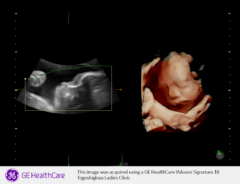

赤ちゃんをよりリアルな画像で確認できる超音波検査

通常の妊婦健診では2D画像による超音波検査です。2Dの通常の画像に立体性を持たせた画像が3D、3Dに動きの要素を加えた画像が4Dとなります

【医師】4Dエコー

【助産師】4Dエコー